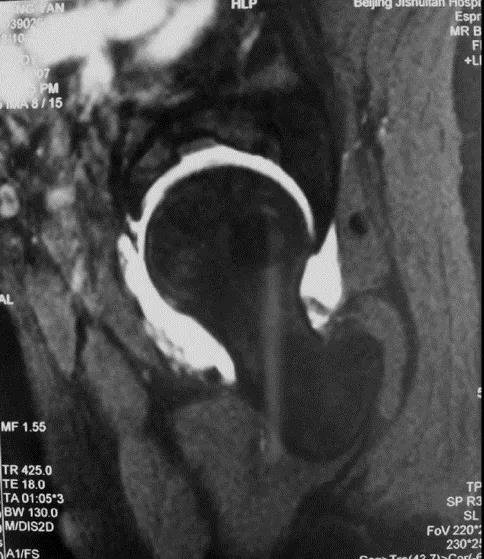

MRI:有不同程度的盂唇撕裂和损伤,对诊断有重要意义

FAI:螯钳型(pincer-type)横断面显示髋臼后倾尤其是上1/3的后倾